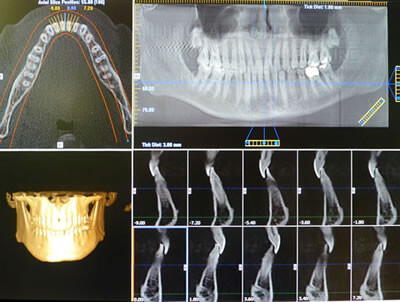

The Clinical Exam of the mouth reveals the health of the teeth and periodontal condition of the patient. Once the Clinical Exam is completed, the most important Dragnostic Tool available today is an X-ray machine that uses Cone Beam Computed Tomography (CBCT) commonly referred to as a CAT scan (CT). This X-ray machine is identical to the CAT scan used for medical diagnosis. The wonderful advantage of the Dental CAT scan is unlike standard dental X-rays that are two dimensional, the Dental CAT scan allows a three dimensional view of the jaws.

This three dimensional view allows the implant surgeon to make a complete evaluation of the bone available for implants. The CAT scan also facilitates the location of anatomic sites such as the sinus areas, nerves and other anatomic sites that the implant surgeon must avoid when placing implants. In other words, the Dental CAT scan permits a more safe and predictable surgical procedure. The implant surgeon can provide a very accurate, precise treatment plan.